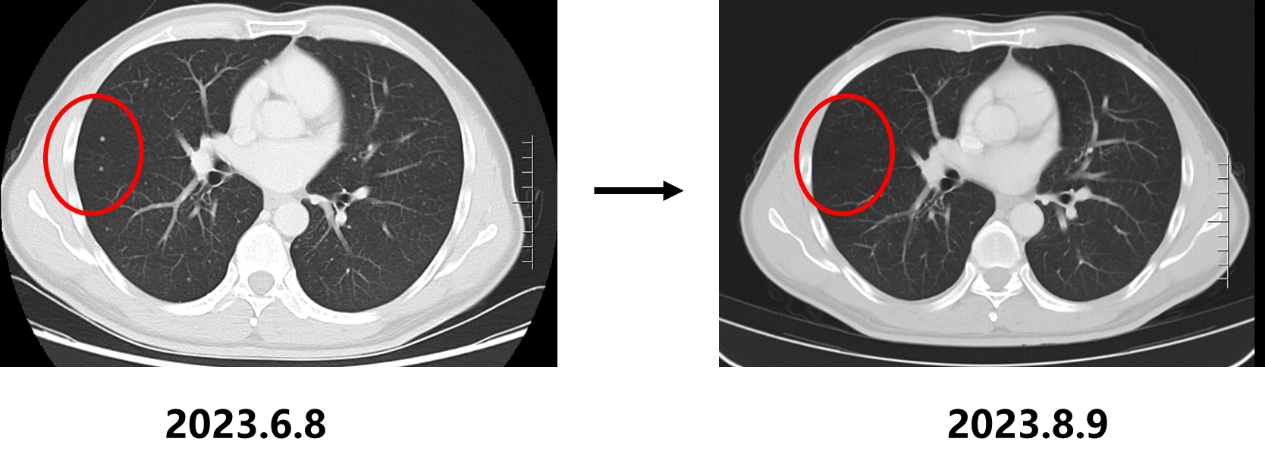

2023.6.8 胸腹部+盆腔CT:1. 胃底贲门部胃壁增厚,考虑胃底贲门癌,并肝胃间隙及腹膜后多发淋巴结转移瘤(大者短径20mm)、双肺多发转移瘤可能性大(大者长径6mm);2. 左侧髂骨、右侧坐骨及骶骨高密度影,考虑骨岛或骨转移瘤。

• 2023.8.10复查CT:胃底贲门部胃壁增厚明显改善,肝胃间隙及腹膜后多发淋巴结转移瘤较前缩小(大者短径17mm)、双肺多发转移瘤较前缩小、减少,疗效评估为部分缓解(PR)。